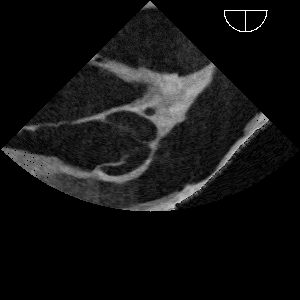

Niewątpliwą cechą wyróżniającą symulator CT2TEE jest symulacja i wizualizacja projekcji echokardiograficznych w oparciu o dane z CT. Oprócz możliwości wykorzystania badań retrospektywnych takie podejście daje dość duże podobieństwo do rzeczywistych badań ultrasonograficznych.